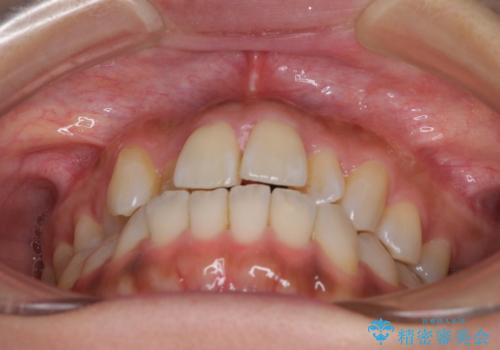

- 上の歯の歯並びを気にして来院された患者様です。

上顎骨の横幅が狭く、歯列が混み合っていたため、急速拡大装置により側方拡大し、咬み合わせと歯列を改善することとしました。

下顎は部分的に咬み合わせに問題があったため、部分的な装置を付けることとしました。